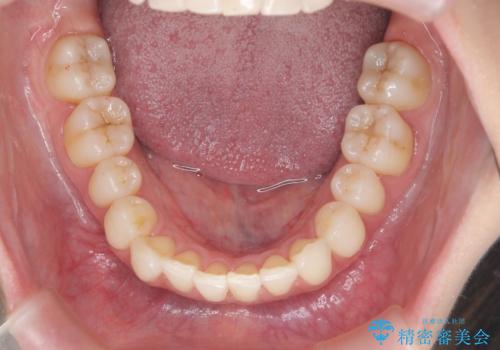

昔ワイヤー矯正をして後戻りした 軽度のがたつき モニター矯正

- 矯正治療後の後戻りを主訴に来院。

特に下の前歯のがたつきを気にされていました。

マウスピース矯正で再矯正を行いました。

再度の後戻りを防ぐため、下顎前歯の裏にはワイヤーを貼る保定を行っています。